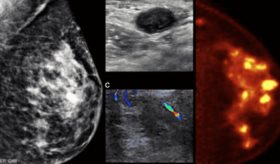

Este avance insurgente en técnicas de imágenes mamarias ofrece una disminución significativa de la posibilidad de obtener resultados "falsos positivos".

El cáncer de seno es la primera causa de muerte en mujeres puertorriqueñas. El miedo y desconocimiento evitan que la detección temprana reduzca las cifras cada año.